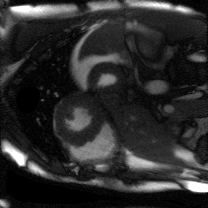

Supervised Deep-Learning (DL)-based reconstruction algorithms have shown state-of-the-art results for highly-undersampled dynamic Magnetic Resonance Imaging (MRI) reconstruction. However, the requirement of excessive high-quality ground-truth data hinders their applications due to the generalization problem. Recently, Implicit Neural Representation (INR) has appeared as a powerful DL-based tool for solving the inverse problem by characterizing the attributes of a signal as a continuous function of corresponding coordinates in an unsupervised manner. In this work, we proposed an INR-based method to improve dynamic MRI reconstruction from highly undersampled k-space data, which only takes spatiotemporal coordinates as inputs. Specifically, the proposed INR represents the dynamic MRI images as an implicit function and encodes them into neural networks. The weights of the network are learned from sparsely-acquired (k, t)-space data itself only, without external training datasets or prior images. Benefiting from the strong implicit continuity regularization of INR together with explicit regularization for low-rankness and sparsity, our proposed method outperforms the compared scan-specific methods at various acceleration factors. E.g., experiments on retrospective cardiac cine datasets show an improvement of 5.5 ~ 7.1 dB in PSNR for extremely high accelerations (up to 41.6-fold). The high-quality and inner continuity of the images provided by INR has great potential to further improve the spatiotemporal resolution of dynamic MRI, without the need of any training data.